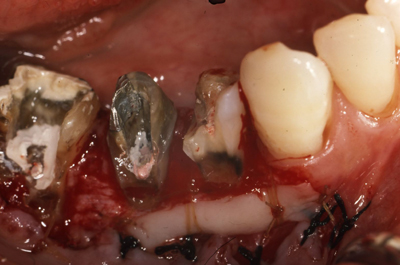

初診から7wブラッシング指導のみ。歯肉に変化はみられますが、あえてまだスケーリングはせずもう少し歯肉が変化するのを待ちます。

さらにその3w後。浮腫性の歯肉が乾いた感じに変化しました。歯肉が治ろうとするサインです!この時を見逃さず、ポケット底から縁上まで1歯につき1回でルートプレーニングをします。